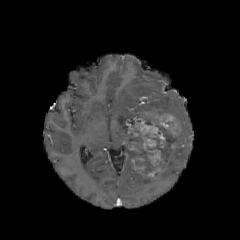

We argue that the sub-optimal paradigm of processing different abstractions within a single CNN pipeline can be remedied through the effective processing of information in a structured manner. Consequently, we devise strategies for disentangling the edge and texture information within a single training pipeline. Figure 2 illustrates how our proposed module, dubbed EG-CNN, can be paired with any existing CNN encoder-decoder to improve segmentation quality near intensity edges. We have applied our EG-CNN to the tasks of brain and liver tumor segmentation in medical images (Figure 3).

(1) Brain MR (2) Liver MR (3) Liver CT (4) Lung CT